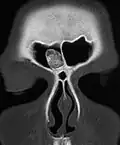

Osteoma of external auditory meatus

An osteoma (plural osteomas or less commonly osteomata) is a new piece of bone usually growing as a benign tumour on another piece of bone, typically the skull. When grown on other bone it is known as "homoplastic osteoma"; on other tissue it is called "heteroplastic osteoma".[1]

Osteoma represents the most common benign neoplasm of the nose and paranasal sinuses. The cause of osteomas is uncertain, but commonly accepted theories propose embryologic, traumatic, or infectious causes. They are present in Gardner's syndrome.